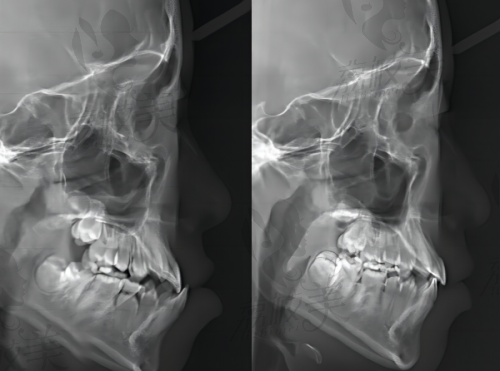

沈阳德立联合口腔医院郑淳奎医生做乳牙拔除+进口麻醉成功实例分享

有一位小朋友叫乐乐,到了换牙期,乳牙一直不掉,恒牙都已经长出来了,形成了“双排牙”。乐乐的家长非常着急,带着他跑了好几家医院,都不太满意。后来听说了沈阳德立联合口腔医院的郑淳奎医生,就抱着试试看的心态来了。郑医生仔细检查了乐乐的牙齿后,决定为他进行乳牙拔除。在拔牙过程中,郑医生熟练地操作着,进口麻醉也发挥了良好的成效,乐乐一点都没有感觉到疼痛。拔牙结束后,乐乐也没有出现肿胀等不良反应,修复得非常快。乐乐的家长对这次拔牙经历非常满意,还把这家医院推荐给了身边的其他家长。像乐乐这样的成功实例还有特别多,这也充分证明了郑淳奎医生和沈阳德立联合口腔医院在乳牙拔除方面的实力。